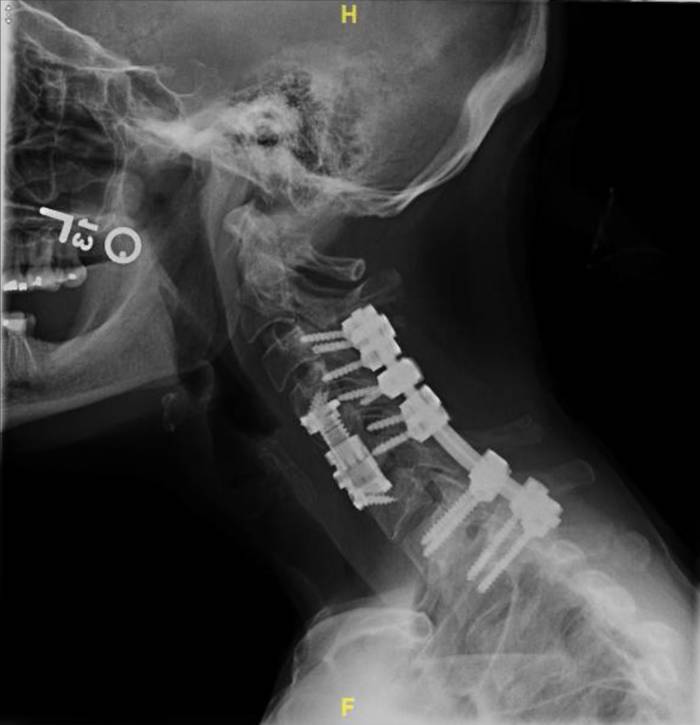

Dr. Ankit I. Mehta’s lab at the University of Illinois at Chicago (UIC MLI) specializes in “the surgical treatment of complex spinal conditions including tumors, degenerative and spine diseases”, among which are corrective surgeries which require screws to be placed in patients’ spines to help correct vertebrae alignment. X-rays are taken at the location of any inserted screws at two occasions - one relatively closer to the operation and another later on - so that movement in screws and/or vertebrae can be monitored over time. At each time, two x-rays are taken: one from the patient’s side (lateral view) and another from the back (AP view). In addition to verifying operation success, the “post” x-rays can help diagnose spinal issues that may have occurred as a result of an operation, such as pseudarthrosis.

For both the lateral and the AP views, there are two separate sources of motion that could contribute to differences between the “pre” and “post” images: movement of the patient and the ovement of the spine and/or screws. The camera itself has preset positions for both views, with millimeter-level noise between separate images that can be effectively ignored. As the movements of the patient are extraneous, they introduce noise that makes it difficult to evaluate patient progress and diagnose any potential issues (e.g. pseudarthrosis) that may cause major health risks. As a result, a patient that may come in after their operation to diagnose why they haven’t seen the expected improvement may require additional x-rays which delay the process, which could result in any medical conditions worsening or potentially another operation being required.

We will create an algorithm enabling users to upload both the “pre” and “post” images, realign/manipulate them, and eliminate noise induced by movement of the patient. By doing so, the lab will be able to make more accurate diagnoses and prognoses of their patients. Having specific, quantitative data on the relative positions and movements of screws and vertebral bodies of interest would help patients to make the best of their own and the lab’s time and diagnose any complications earlier for better health and less cost to the patient.